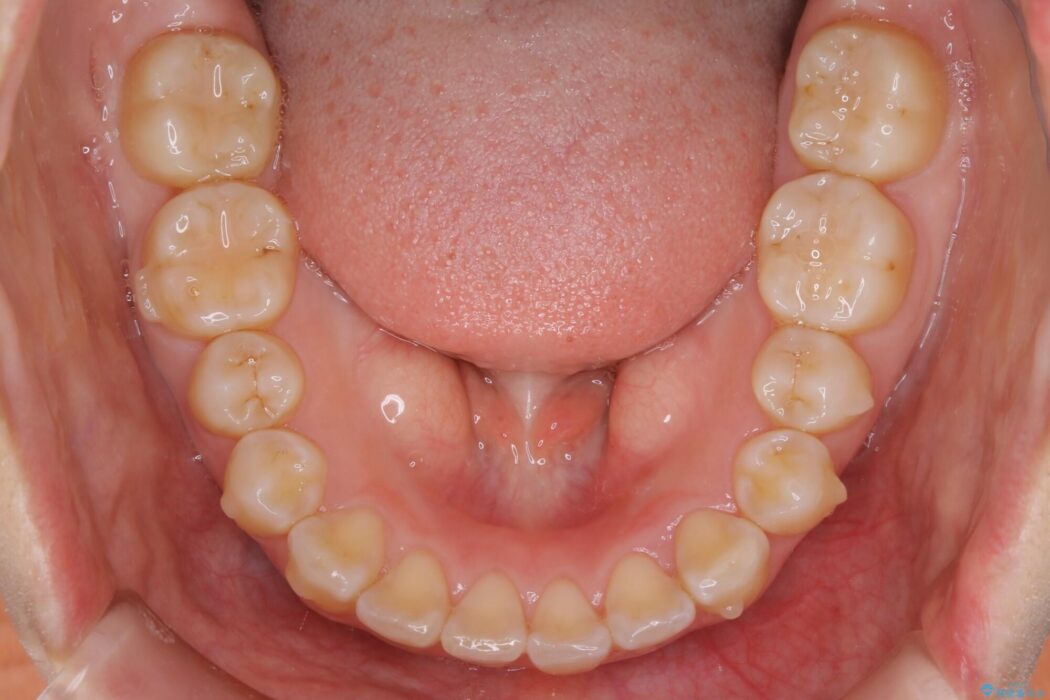

噛み合わせの違和感と前歯のガタガタを主訴に来院されました。

歯軸傾斜と軽度の叢生が見られましたので、通常の位置へと傾きを戻し少量の遠心移動に加えアーチ(歯列弓)の拡大とIPRを施すことで改善していく非抜歯での治療計画としました。